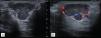

Plain radiographs (Fig. 1), ultrasound (Fig. 2), and magnetic resonance imaging (Fig. 3) were requested.

The ultrasound description of the GCTST is a hypoechoic, heterogeneous lesion, with Doppler, related to the affected tendon. On MRI it presents as a lobed lesion, of intensity in T1 and T2 which, in STIR, show intense enhancement. Determination of hypointense haemosiderin foci is useful in differentiating these from other lesions.